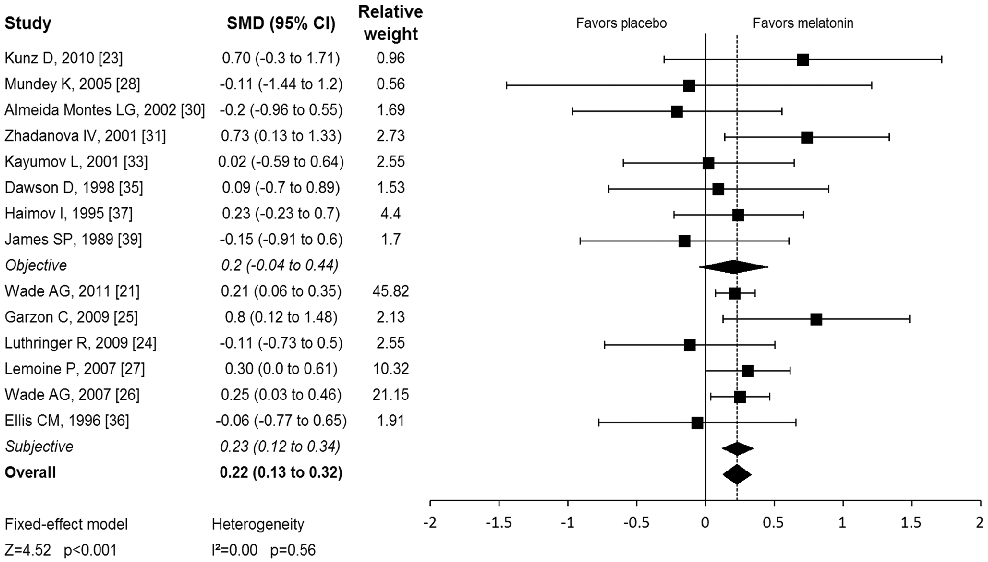

Pooled effect estimates for melatonin's impact on total sleep time and sleep quality across randomized controlled trials are presented, with subgroup analyses by dosage and duration.

Meta-analysis: melatonin for the treatment of primary sleep disorders.